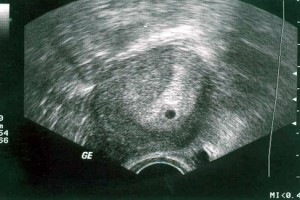

УЗИ плода. УЗИ на третьей неделе беременности по акушерским расчетам еще не информативное, его обычно назначают при специфических симптомах, чтобы исключить внематочную беременность. Врач может увидеть плодное яйцо и определить место его крепления, но провести диагностику развития эмбриона или определить его пол еще нет возможности. Ребенок на третьей неделе беременности размером всего 0,1–0,2 мм. Исследование позволит оценить состояние мышечной ткани матки и органов малого таза, а также спрогнозировать течение беременности. Увидеть, какой ребенок на третьей неделе, не получится, на фото видны только органы мамы.

УЗИ на 13-й неделе беременности покажет очертания и размеры малыша, его шевеление. Кроме того, с помощью ультразвукового исследования доктор сможет оценить состояние матки, предлежание и место прикрепления плаценты, установить приблизительный срок родов.